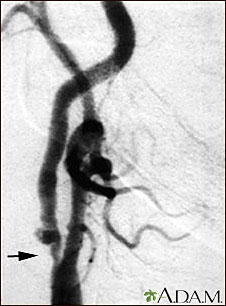

Estenosis carotídea; radiografía de la arteria derecha

Angiograma de la arteria carótida derecha que muestra un estrechamiento severo (estenosis) de la arteria carótida interna justo más allá de la bifurcación carotídea. En esta diapositiva se ve un agrandamiento de la arteria o ulceración en el área luego de la estenosis. Obsérvese el segmento estrecho cerca del extremo inferior de la imagen.